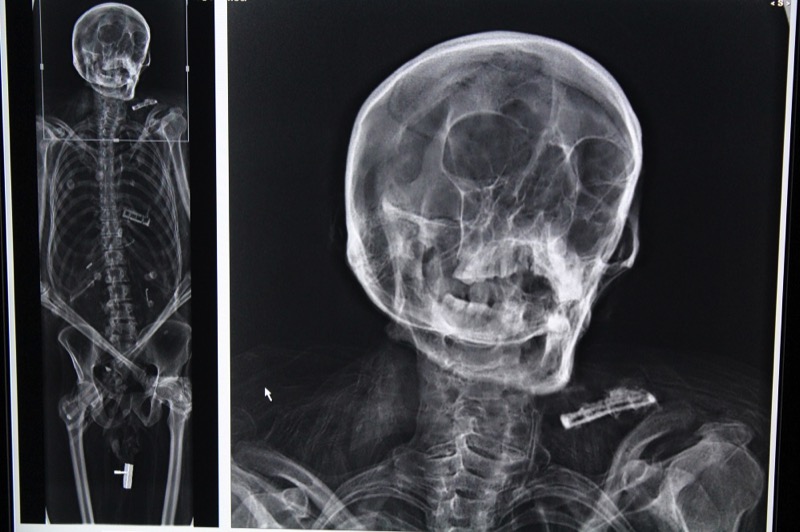

I corpi mummificati, entrambi appartenenti a soggetti di sesso maschile ed in ottimo stato di conservazione, sono stati sottoposti ad accurata ripulitura esterna e ad indagini di tipo conservativo mediante radiologia digitale e tomografia computerizzata (TAC). In base all’abbigliamento, l’epoca della morte potrebbe risalire, rispettivamente, alla prima metà dell’Ottocento (1810-30) ed alla fine del Settecento.

Il soggetto ottocentesco, dotato di capigliatura e barba riccia, aveva età di circa 40 anni, costituzione robusta e longilinea, ma appariva eccezionalmente magro. La presenza di noduli polmonari e diffuse aderenze pleuriche a sinistra, dimostrata dalla TAC, lasciava supporre l’ipotesi di un malato terminale di tubercolosi. L’altro individuo, di età anziana (circa 75 anni) e di corporatura robusta, presentava numerose pieghe cutanee, che nelle mummie indicano stati di obesità patologica. Risultava, inoltre, affetto da numerose patologie: usura dentale e parodontopatia marcate, calcolosi addominale destra (della colecisti o del rene) ed una grave artrosi della colonna vertebrale e dell’anca di destra, che doveva rendere pressoché impossibile la deambulazione. Tale condizione doveva provocargli dolori insopportabili, trattati mediante diversi accorgimenti. Erano infatti presenti una fasciatura sul ginocchio sinistro, una foglia (edera?) sulla gamba destra ed uno spessore in materiale argilloso sul piede destro.

Anche questo soggetto presentava noduli polmonari ed aderenze pleuriche diffuse, indicativi di tubercolosi. Inoltre, il riscontro di un’ampia ferita del torace destro, con relativo pneumotorace, potrebbe suggerire un intervento terapeutico eseguito alcuni decenni prima che Forlanini perfezionasse la pratica o, con minor probabilità, una ferita penetrante da arma da punta. Il riscontro di ulteriori casi di tubercolosi polmonare in mummie sette–ottocentesche (analoga condizione fu riscontrata nella “Regina dei Mori” di Scicli qualche anno fa) conferma l’impatto devastante che questa malattia infettiva deve avere avuto in passato sulla popolazione siciliana.